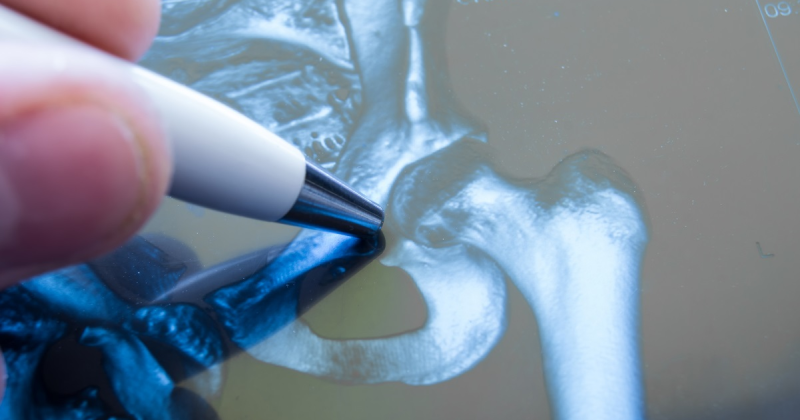

Necroza capului femural apare atunci când articulația șoldului nu primește suficient sânge pentru a funcționa corespunzător. În această situație, osul din capul femurului începe să se deterioreze și să moară. În mod obișnuit, persoanele cu un risc crescut de a dezvolta această afecțiune sunt cele care suferă de alte probleme medicale care pot duce la necroză ischemică, cum ar fi boala de Cheson, anemia cu celule falciforme, boala Gaucher, sau cele care au avut accidente precum luxații sau fracturi de șold.

În stadiile avansate ale necrozei aseptice a capului femural, intervențiile chirurgicale reprezintă cele mai eficiente metode de tratament. Dacă necroza aseptică a capului femural este identificată într-un stadiu incipient, atunci ea poate fi tratată și rezolvată fără proceduri complexe, cum ar fi înlocuirea articulației șoldului.

În astfel de cazuri, decompresia capului femural sau oxigenoterapia hiperbară sunt suficiente pentru a opri progresia bolii și pentru a preveni dezvoltarea coxartrozei. Procesul de recuperare după intervenția de decompresie a capului femural durează câteva luni, iar pacienții trebuie să folosească cârje pentru a evita suprasolicitarea articulației de șold.